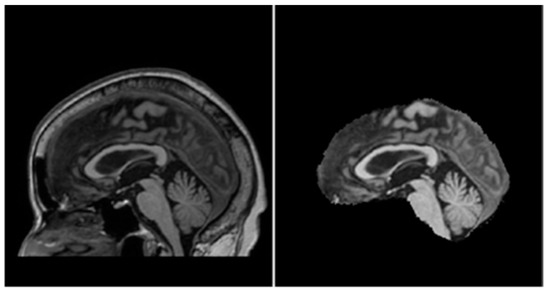

Removal of irrelevant tissues such as those of the eyes, nose, and mouth from brain MRIs, also known as skull-stripping, is essential in reducing the amount of noise within each MRI volume. Iglesias et al. [42] proposed an automated skull-stripping algorithm known as ROBEX that was shown to produce reliable segmentations of the tissues belonging to the brain. With the ROBEX algorithm, all MRI scans in the dataset were skull-stripped to obtain volumes containing just the brain tissues; an example is shown in Figure 7.

Figure 7.

Before (left) and after (right) performing ROBEX skull-stripping.